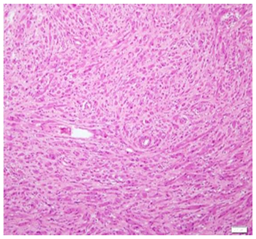

An excision biopsy specimen from a mass at elbow of 26 years old female patient was received for histopathological examination. The clinical impression was of ‘benign soft tissue tumor’. The specimen was received in 10% formalin in one container. On gross examination, it was a 1.5 x 1 x 0.5 cm well-circumscribed, grey-tan mass, without skin component. The cut surface was solid homogenous and no necrotic or hemorrhagic areas were found on it. The microscopic examination revealed a circumscribed encapsulated lesion composed of round to polygonal to spindle shaped cells with eosinophilic granular cytoplasm and centrally placed small nuclei (Figure 1 & Figure 2). Cells were arranged in intersecting bundles and mixed with fibrous connective tissue (Figure 3). The Intralesional peripheral nerve bundles surrounded by the lesional cells were seen (Figure 4). No significant mitoses or cells with cross striation, significant inflammatory infiltrate or necrosis were seen. IHC showed positive results for S100 (Figure 5) and neuron-specific Enolase (NSE) (Figure 6). Smooth muscle actin (SMA) (Figure 7) and Myogenin were negative. CEA was focally positive. Periodic acid-schiff (PAS) stain showed PAS positive intracytoplasmic granules (Figure 8). The lesion was completely excised with <1mm safety margin. Focal entrapment of the adjacent fatty tissue was observed. Based on the above mentioned findings, diagnosis of granular cell tumor (GCT) was made.

The histopathological differential diagnosis of GCTs includes atypical or malignant GCTs, rhabdomyoma, granular cell leiomyoma, hybernoma, xanthoma and reactive changes associated with trauma. Malignant GCTs are very rare, comprising <1% of total GCTs. The histologic criteria to differentiate the benign GCTs from their malignant counterpart include: presence of necrosis, spindling of the cells, vesicular nuclei with prominent nucleoli, nuclear pleomorphism, high N/C ratio and increased mitoses (>2/10 high power field).4,8,9 GCTs with three or more of these criteria are classified as malignant and as atypical if they have two of these features. The presented case showed (focal) spindling of the cells but without any other criteria of malignancy. We preferred to call it as benign GCT. The patient has recurrence free follow up for last four and half years. Absence of cross striations, presence of cytoplasmic PAS positive granules and S100 positivity differentiate GCTs from rhabdomyoma. Negative SMA and positive S100 rule out granular cell leiomyoma. PAS positive granules, S100 positivity and NSE positivity help to distinguish it from xanthoma. Absence of inflammatory infiltrate and IHC finding distinguish reactive lesion with granular cells from GCTs. Recommended treatment for GCTs is surgical excision with free surgical margins.5,10,11 Recurrence rate is very low for benign GCTs.